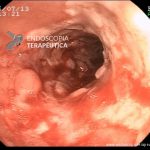

Colite por Doença de Crohn

- Doença de Crohn em atividade – proctite